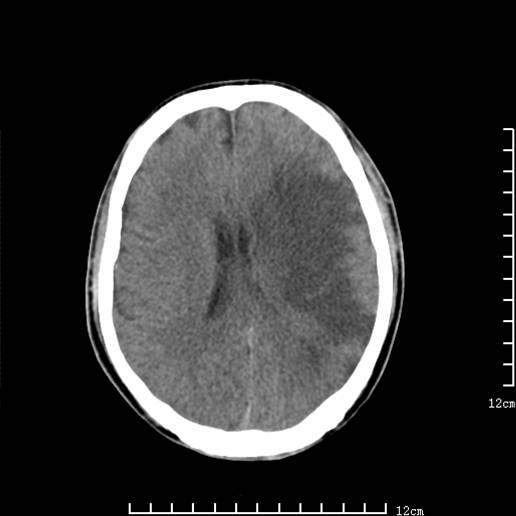

以下图像分别是3月25日凌晨及下午图像、3月27日、4月16日的ct图像。

3月25日下午

脑梗塞(左侧大脑中动脉分布区)。

1)左侧额颞顶叶、岛叶及基底节区(相当于左侧大脑中动脉供血区)大面积脑梗塞。2)右侧基底节区腔隙性脑梗塞。